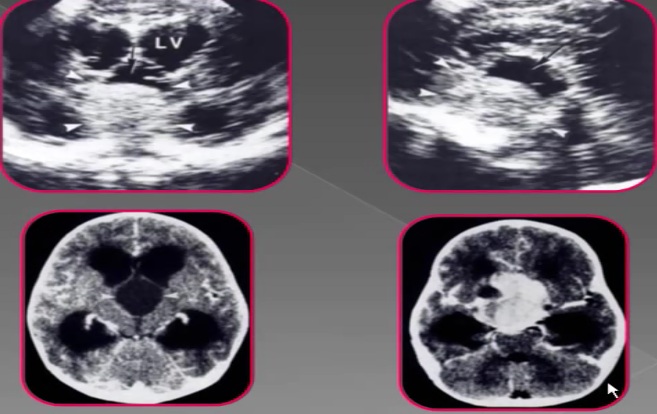

颅脑超声

新生儿头部超声